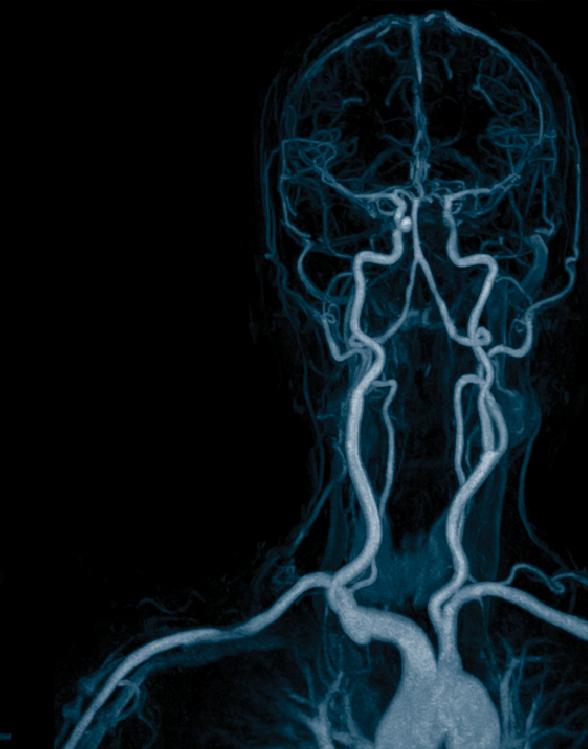

I mages from the embolectomy procedure performed on the patient whose CT perfusion image is on the cover. Both the “before” and “after” are lateral projections with the x-ray camera positioned over the patient’s head.

The “before” image has a paucity of blood vessels because there is a blood clot in the middle cerebral artery that is occluding flow into all of the branches from the middle cerebral artery. The “after” image was obtained after the embolectomy procedure was performed to remove the blood clot in the middle cerebral artery. This shows restoration of normal blood flow to the brain.

Comparing the “before” and “after” images shows the very large number of blood vessels, and subsequent area of the brain, that were at risk of causing permanent stroke for the patient. Thankfully, the blood vessels were able to be reopened in time and the patient made a full recovery.